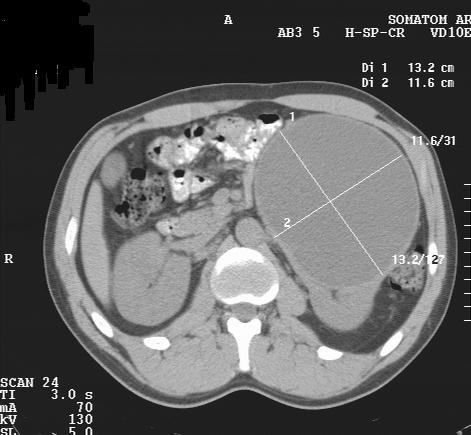

М. 37 лет, жалоб нет, амб. приём, причина назначения УЗИ ОБП: СОЭ 42мм

б\б и м\э консист., как говорится.   Исходит из н\ полюса левой почки

КТ сделали без контрастирования, смысл такого КТ??? Диагностической ценности-ноль.